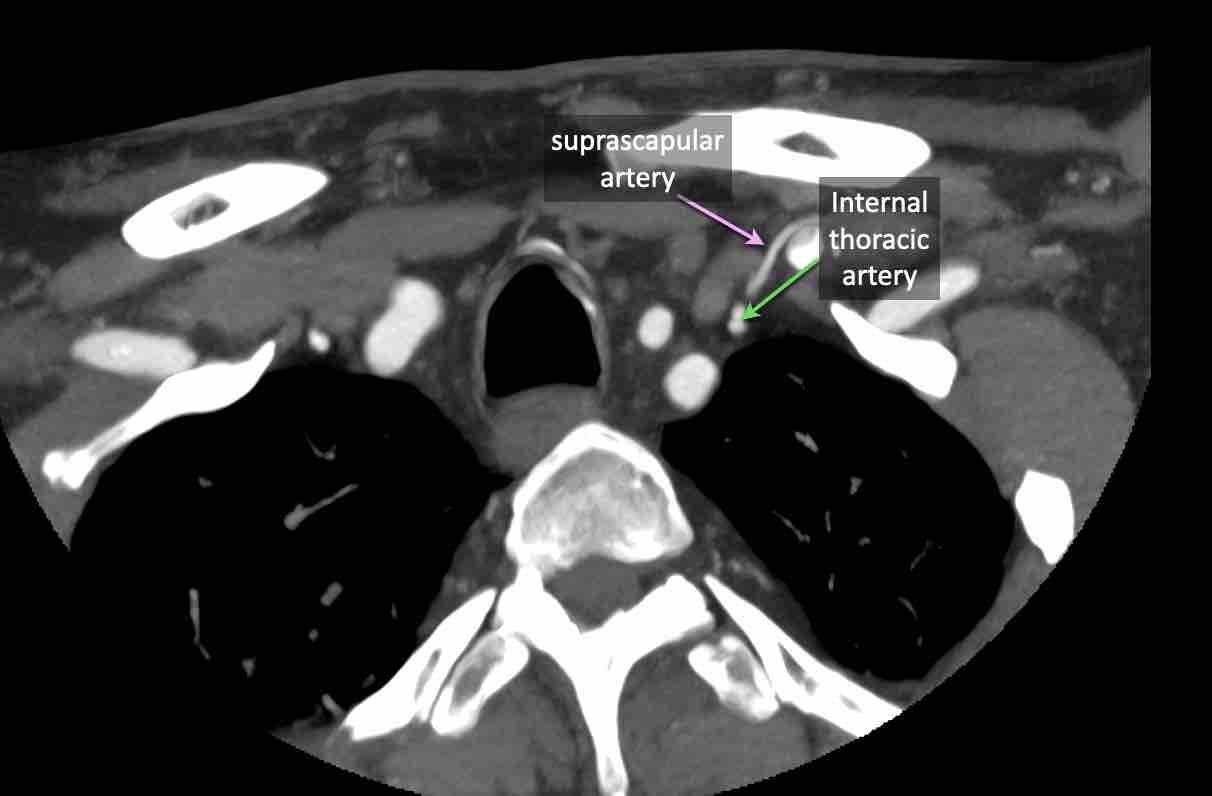

Động mạch cổ ngang

Cuộn qua các hình ảnh để xem giải phẫu của động mạch cổ ngang.